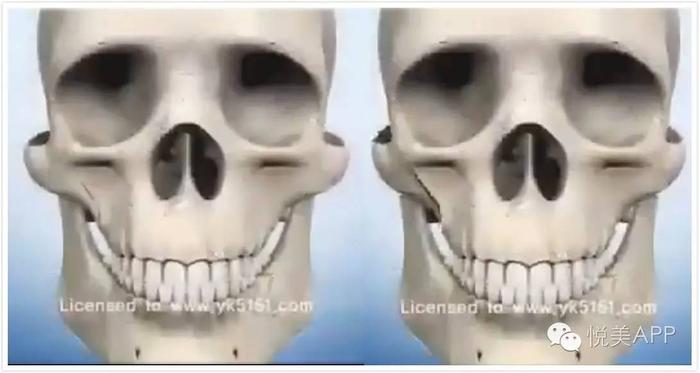

首先我们来了解一下颧骨内推的术式

总的来说颧骨手术就是:前方从口腔内切口进入,后方从耳前切口进入,剥离开截骨部分组织之后,在骨膜下方操作,截骨后固定。

颧骨部位L型切口,去掉部分骨头,如图示

向内推移,并前后用钛钉固定

最后呈现颧骨降低,正面脸变窄的效果